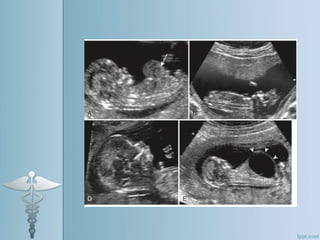

Standardization of Nuchal Translucencymeasurement technique 1. Callipers must be able to be adjusted in increments of 0.1 mm 2. Approximately 20 mins. should be given to obtain required measurements 3. CRL must be between 38-84 mm 4. Clear NT margins 5. Fetus horizontal image 6. Fetus in mid sagittal plane

• 25.

7. Tip ofnose in profile 8. Head , neck and upper thorax should fill the image with no visualization of heart. 9. Head in Neutral Position 10. Pocket of fluid should be visible between chin and neck 11. Angle of neck and chest should be <90 deg.

• 26.

12.Callipers are placedat inner border of lucent line 13. Lucency measured perpendicularly and in widest space 14. Measure NT three times and report the largest of three technically correct measurements.